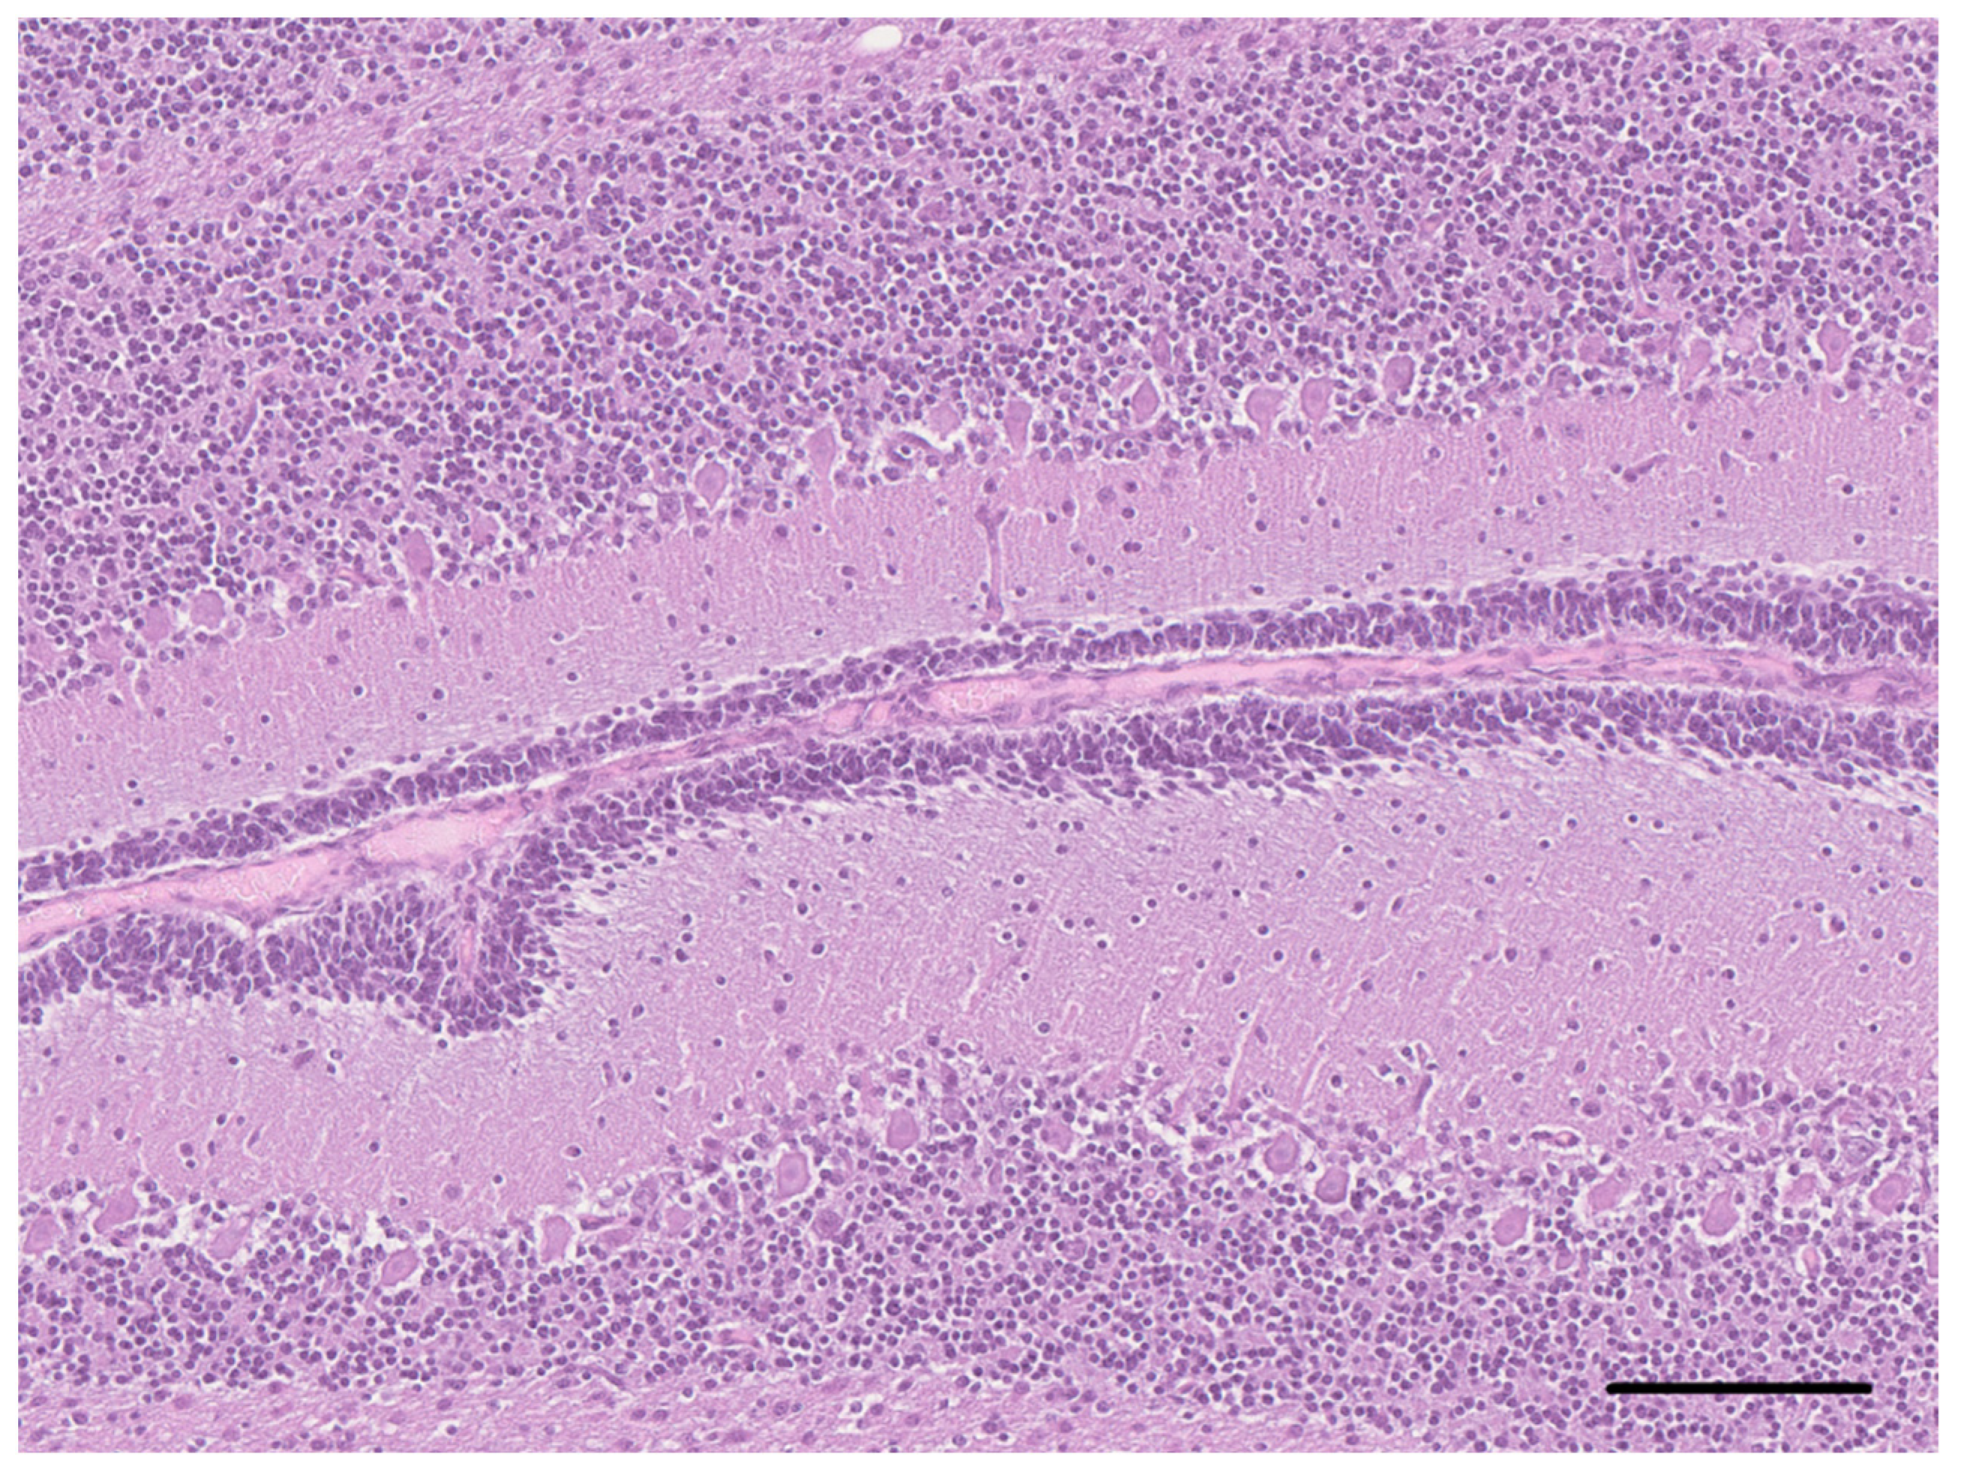

2. Case Description